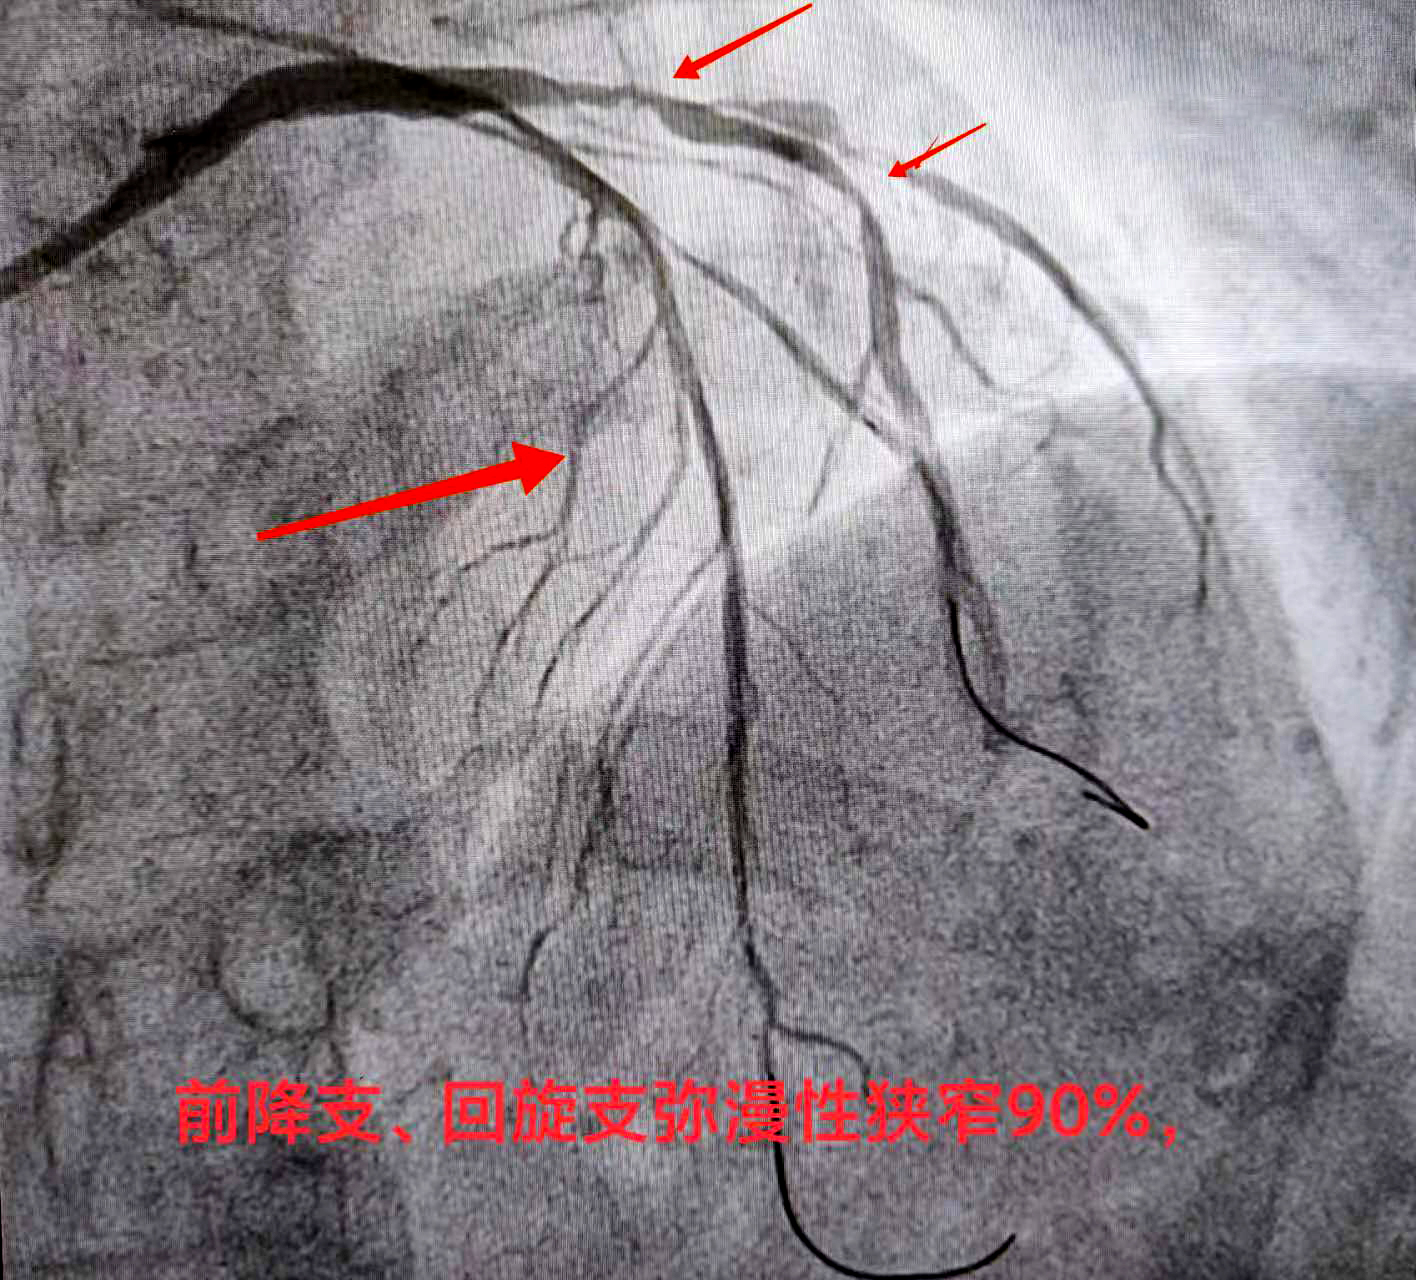

熊斌主任在接诊后立即为赵某做相关检查,结果显示严重三支病变——即为心脏供血的三条大血管前降支血管、回旋支血管、右冠状动脉,甚至包括左主干都存在狭窄病变,狭窄程度达90%以上,属于弥漫性狭窄病变。通俗地讲,就是赵某的冠脉血管近乎全都堵塞不通,血液无法顺畅供给心脏,这导致了心脏缺血,从而引起胸闷、胸痛、心慌气短等不适症状,严重者还会导致心肌坏死、心梗发生,严重威胁生命健康。

经检查,赵某恢复良好,身体状况符合再次开展介入的条件,因此医院很快为赵某安排了手术时间。“依据我们根据患者病情制定的治疗方案,这一次针对前降支血管开展支架介入。”熊斌主任介绍,根据赵某的血管具体情况,此次介入仍是在杨胜利教授的指导下,在赵某的前降支血管植入两枚药物洗脱支架,支架贴壁膨胀良好,血管得以顺利开通,血流得以恢复,而且支架上携带的药物也能起到预防支架内再狭窄的作用。同时,科室在脉络学说指导下,发挥中西医结合诊疗优势,在常规西药加支架治疗基础上加用通络药物,显著降低心梗支架术后心肌无复流发生率,改善心肌微循环血液灌注,保护心肌,减少心室重构,避免向慢性心衰发展,从而改善心梗支架植入患者的远期预后。